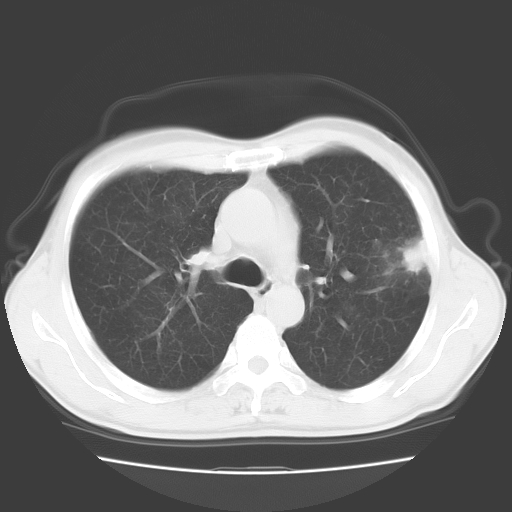

以下是引用随光逐影在2008-11-20 23:02:00的发言:[br]1)考虑左肺上叶周围型肺癌可能性大。2)两肺散在性肺泡积血。[br][br][本贴已被 随光逐影 于 2008-11-20 23:09:31 修改过]

以下是引用drzhang8888在2008-11-20 22:20:00的发言:[br]密集的短毛刺,血管集束,胸膜凹陷,周边型肺癌可能性大,另双肺多发磨玻璃影,考虑感染

以下是引用流浪星在2008-11-20 22:28:00的发言:[br]左肺上叶近外围区见一类圆形结节影,毛刺征、胸膜尾征阳性,临近肺组织见多发渗出灶。考虑1,炎症性病变。 2.周围性肺癌。建议抗炎治疗后复查。

以下是引用qc80012345在2008-11-21 5:53:00的发言:[br]支持;周围型肺癌诊断。增强扫描。